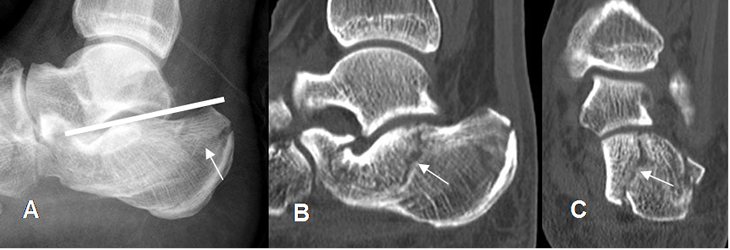

Fig 46 A. Fractura de calcáneo.

A: Rx lateral, B: TAC reconstrucción lateral y C: TAC reconstrucción coronal.

Fractura impactada y conminuta del calcáneo, con ángulo de Bohler plano.